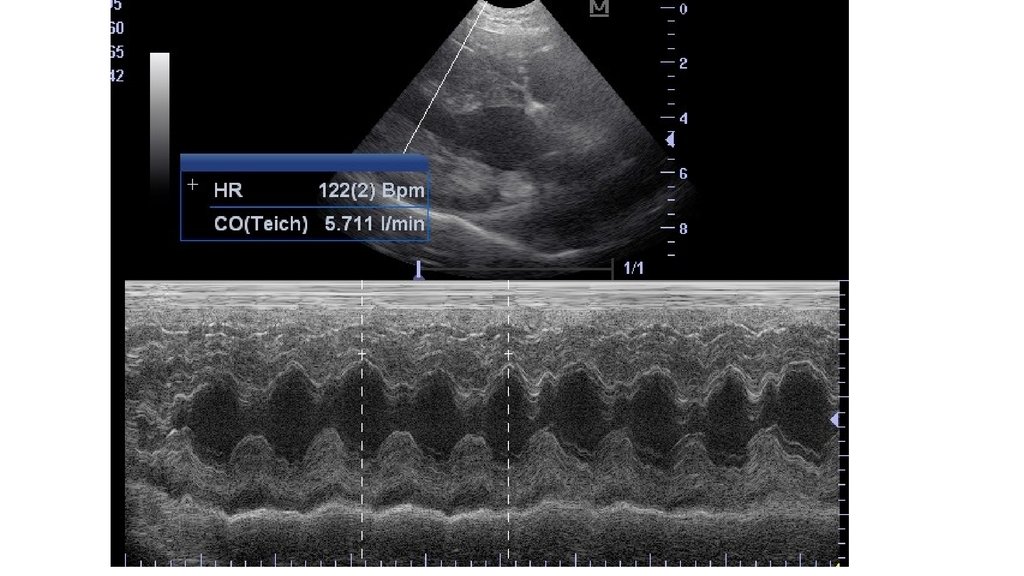

Подсчет ЧСС в м-режиме.

• Вывести в В-режиме желудочек, чтобы хорошо были

видны его сокращения

• Провести линию М-режима в зоне с наилучшей

видимостью стенок и полости желудочка.

• Зафиксировать и сохранить полученное

изображение.

• Пометить частоту сердцебиений (НR), от пика к

пику или от впадины к впадине.

• Аппарат автоматически рассчитает ЧСС.